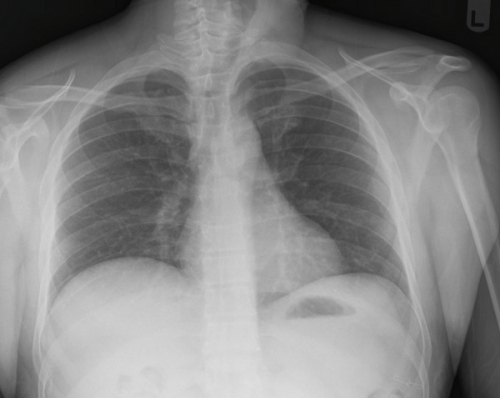

Tool to train medical student's eyes as to what a normal chest x-ray looks like, with over 500 consecutive normal images.